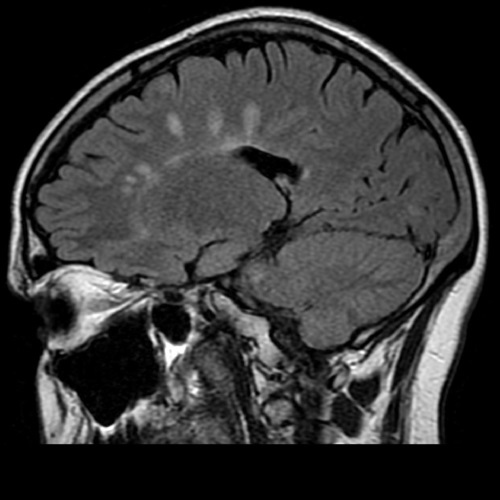

what are the typical imaging findings in MS?

periventricular white matter lesions seen on MRI (T2)

what are dawson fingers?

• radiological sign in MS

• seen on FLAIR images

• hyperintense lesions penpendicular to the corpus callosum